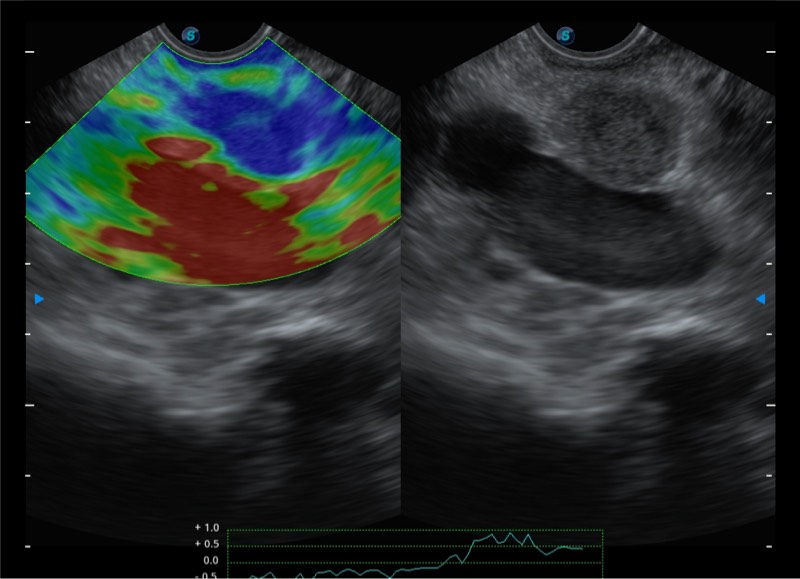

基于二十年的超声技术积累,诸侯快讯官网提供了最新一代的独立超声主机,在提供高质量图像的同时满足多学科使用。具备常见多普勒技术并提供弹性成像、声学造影等高端影像技术。新一代传感器具有更强的抗干扰能力并减少图像伪影。

150°超声扫描角度

4-12MHZ宽频输出